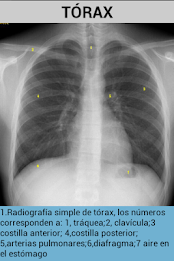

Tato aplikace se naučí snadno identifikovat anatomické struktury, které lze vidět v radiologii.obsahuje obrázky prostých rentgenových snímků, MRI a CT skenů.

Také s každým obrázkem je vysvětlení, které lépe porozumí.

obsahuje obrázky hlavy, páteře a hrudníku.